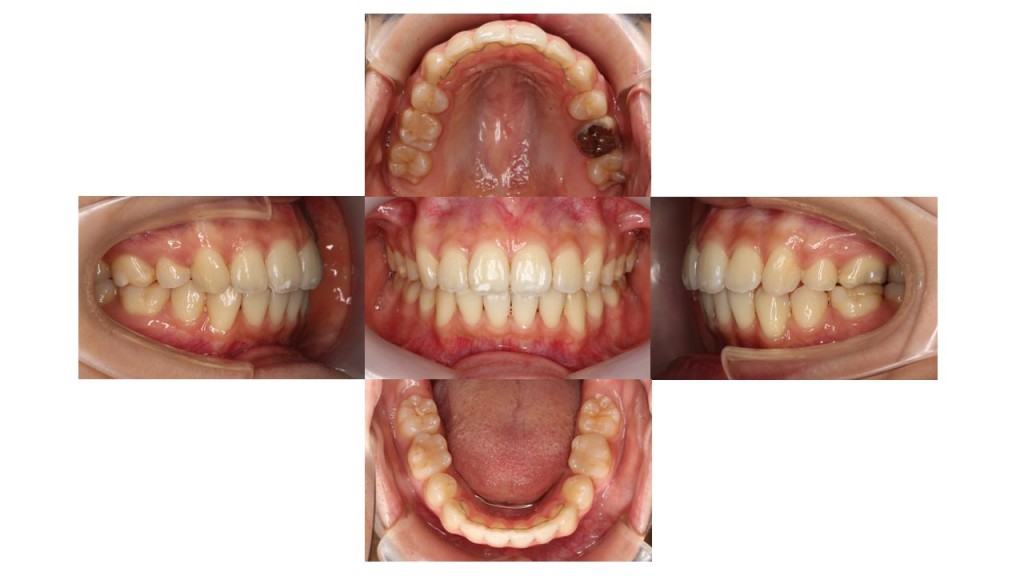

1年8ヵ月経過の口腔内の状態です。

動かす期間は終了したため、前歯部分に固定タイプの保定装置を装着しております。

前歯のかみ合わせが改善し、お口も閉じやすくなったとご満足いただけました。